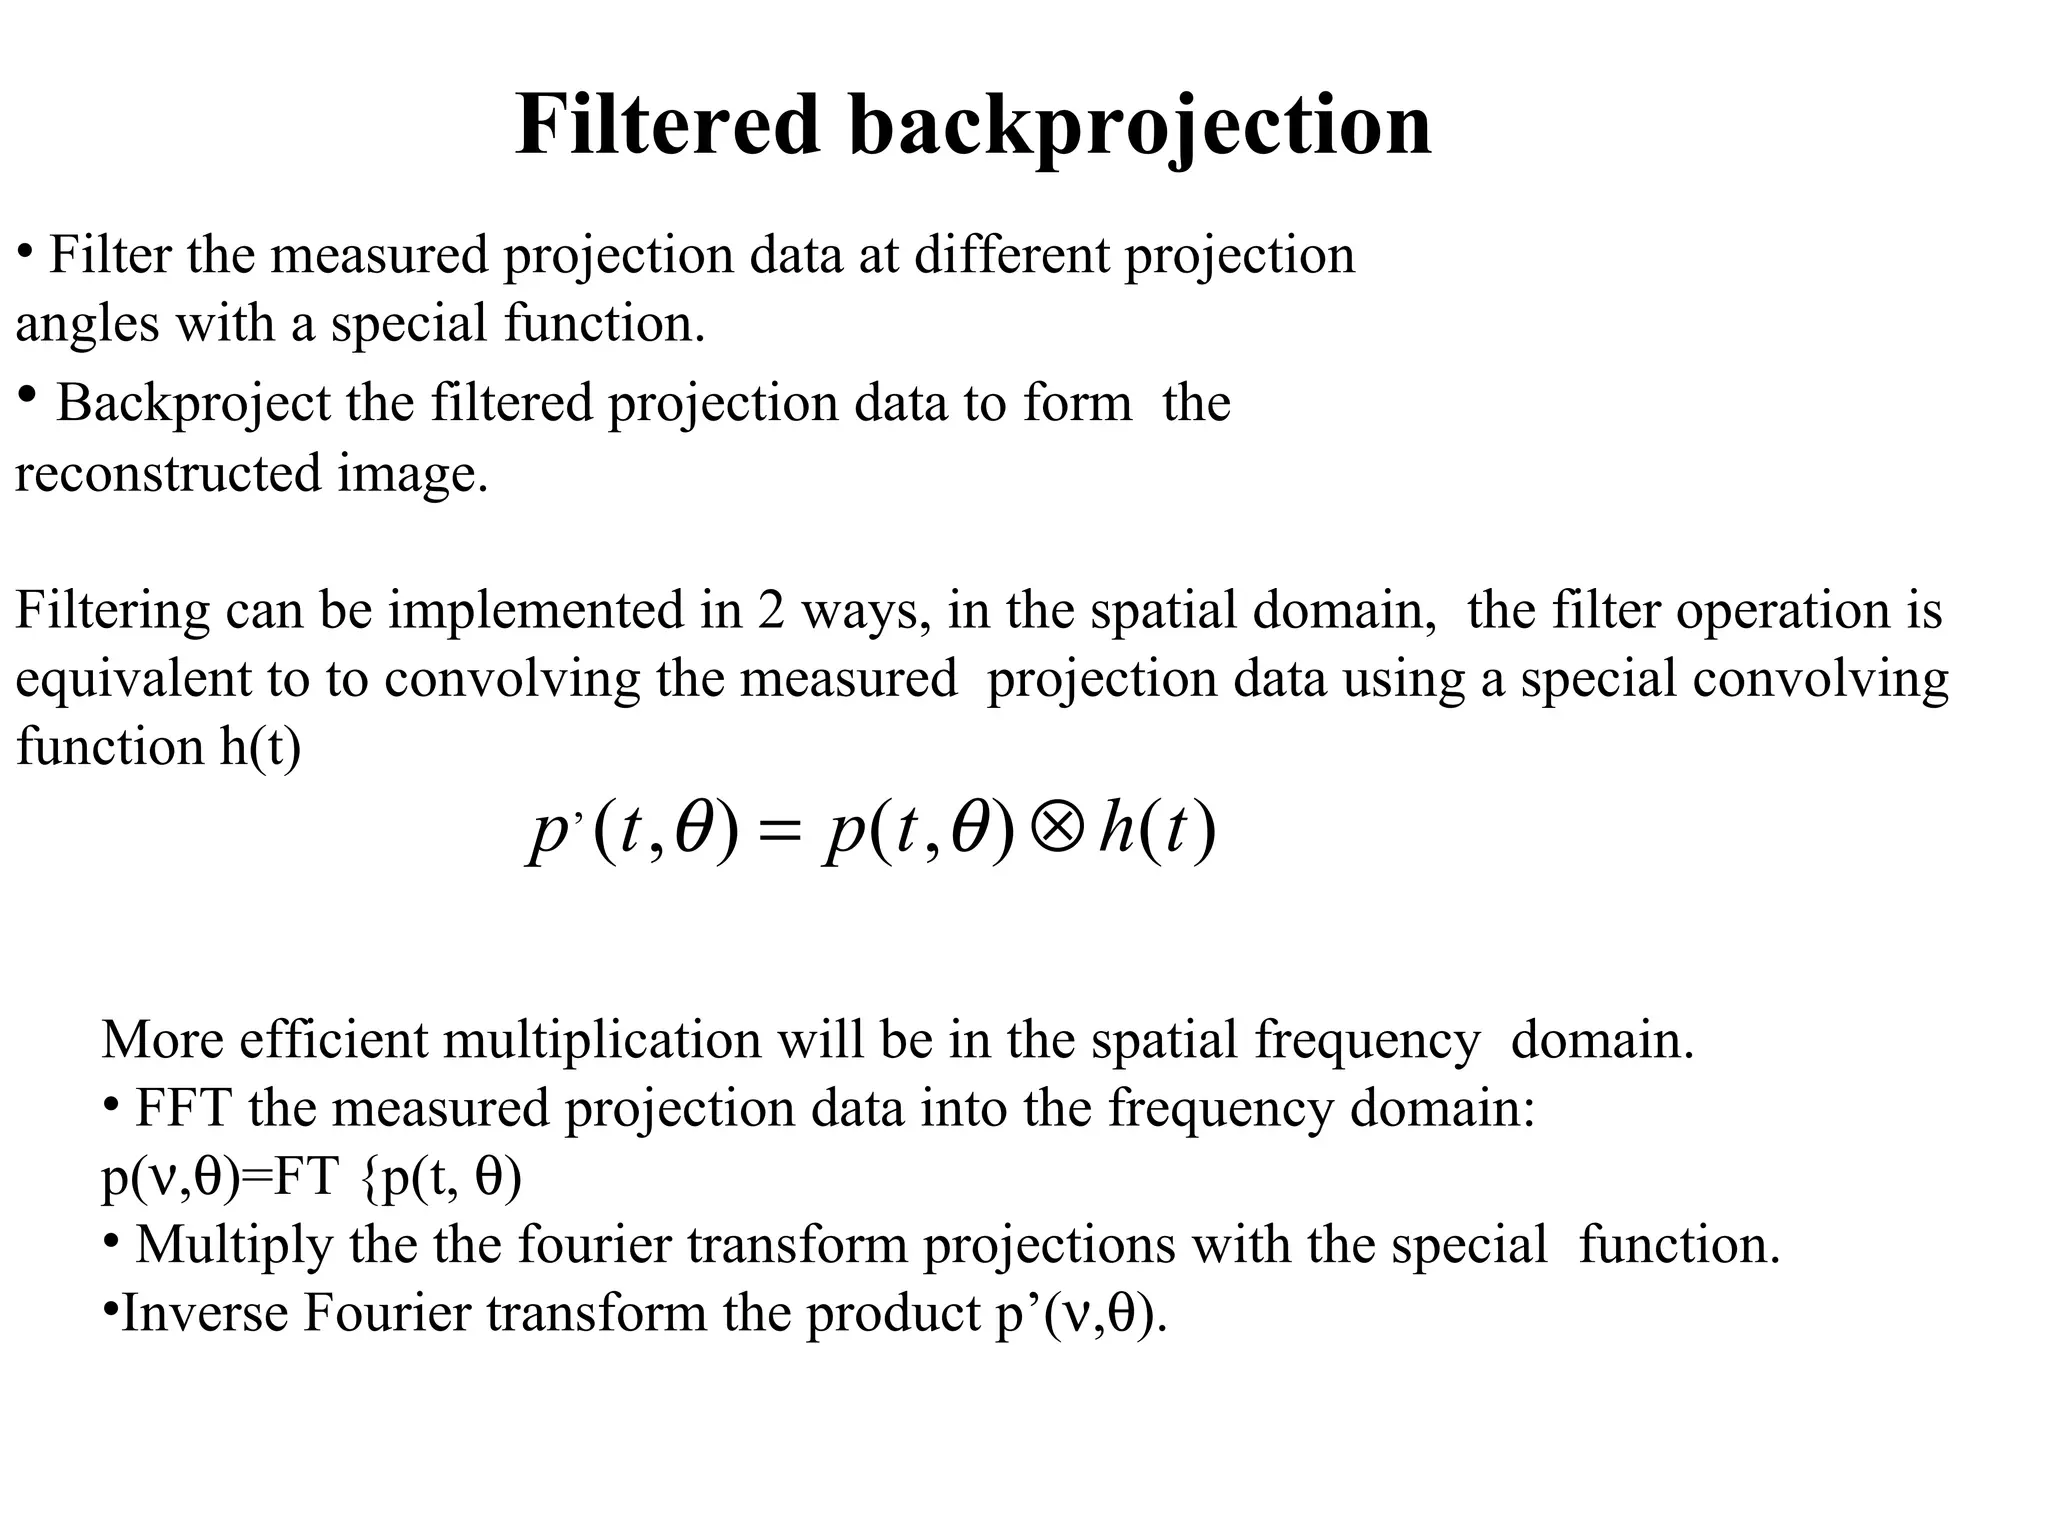

The document discusses various medical imaging modalities including x-rays, computed tomography (CT), and digital mammography. It describes the basic principles and historical development of these technologies, how images are formed, and what types of anatomical features and abnormalities they can detect. Key advances include the development of digital systems that allow image manipulation and remote consultation. While promising, digital mammography still faces challenges around resolution and cost.